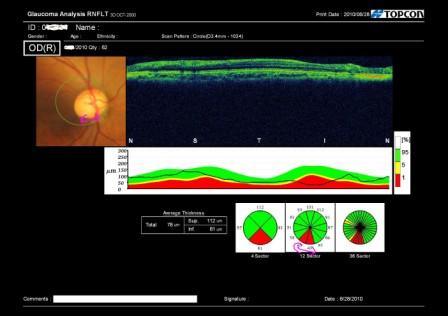

精密検査で視神経の周りの神経繊維層を分析してみると、

やはり両目とも神経の量が減っています。(上記の写真の赤色で示された部分)